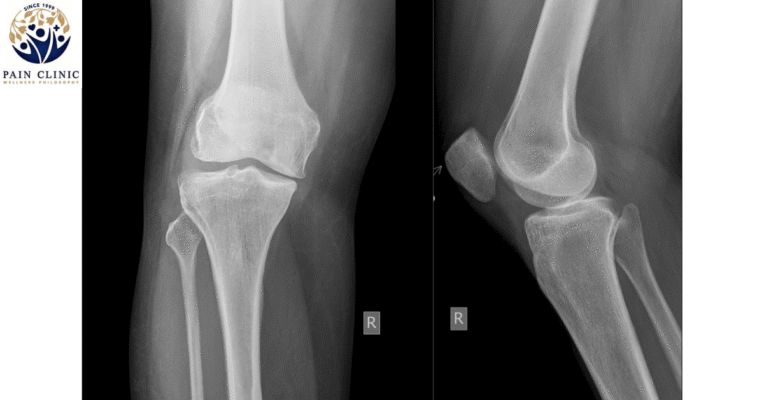

- Pain at the front, behind or around the kneecap.

- Going for a check up for your bone’s structure to identify any mis-alignments can help you have a better understanding of your body’s condition. You can then put in place preventive measures to reduce and prevent further aggravation of symptoms. Preventive measures include anti-inflammatory medicine or a cask that may help align or protect your bone structure.